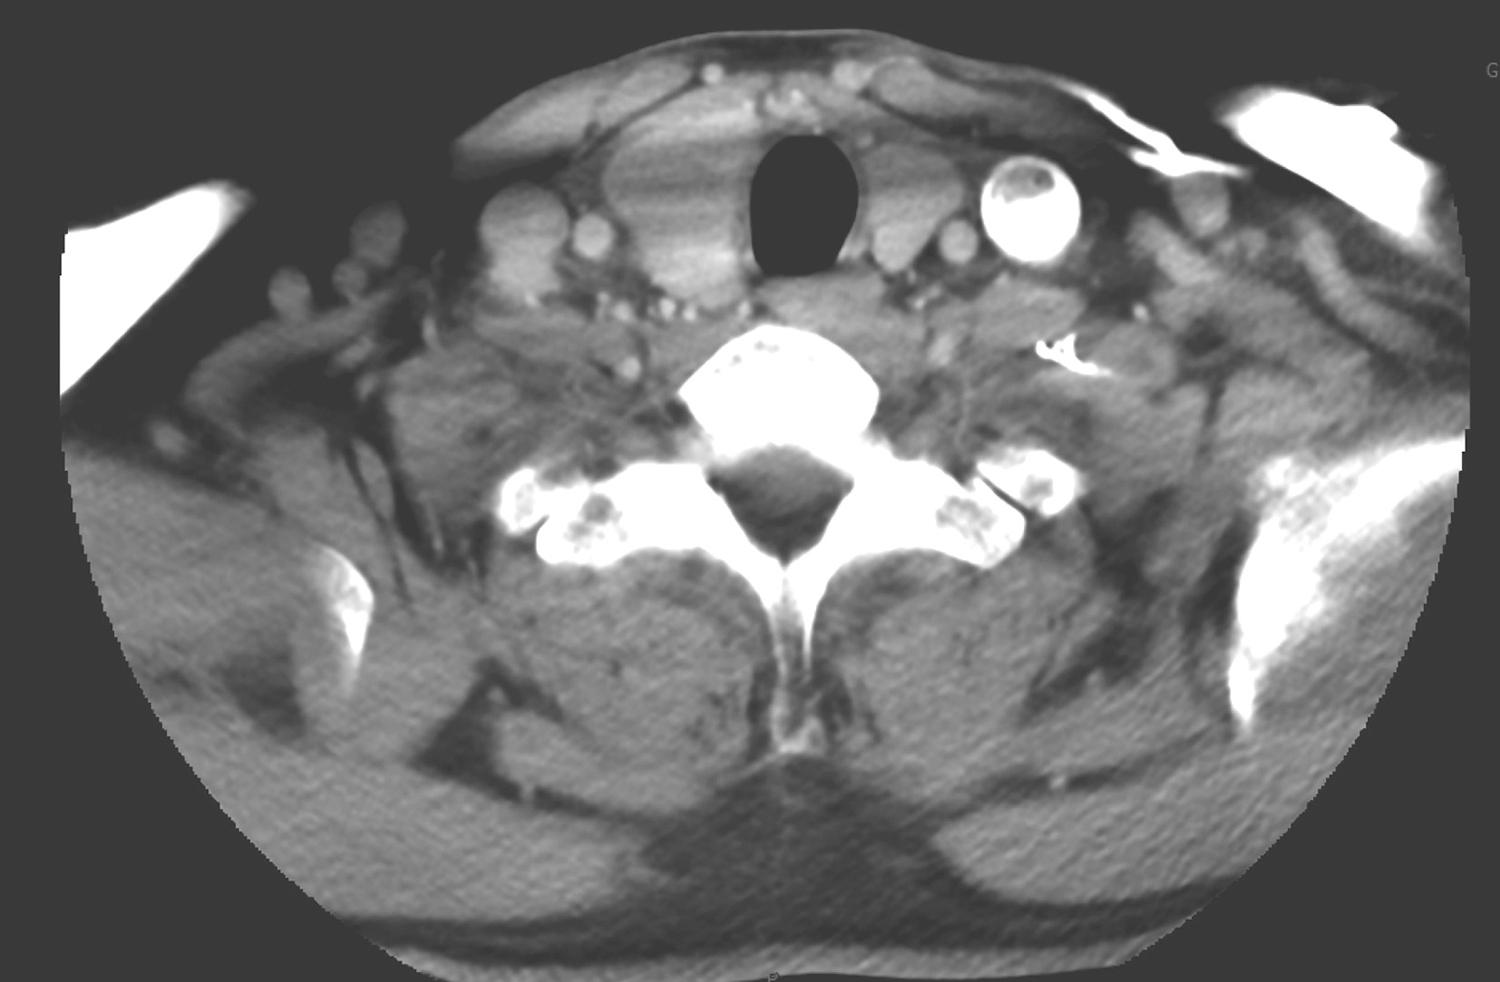

2.2017年5月15日颈胸部CT

甲状腺右叶低密度结节,约3.2cm×2.2cm,边界欠清楚,右侧气管壁受压,管腔受压略左移(图3);右侧气管食管沟、双侧锁骨上区及上纵隔多发淋巴结影,大者短径约1.5cm(图4);双下肺条索影,余双肺及纵隔未见明确结节或实变;双侧肺门未见明确肿大淋巴结;双侧胸腔、心包未见积液。

图3 颈部CT示甲状腺右叶低密度结节致气管壁受压左移

影像学诊断:

(1)甲状腺右叶低密度结节,考虑为恶性,请结合超声观察。

(2)右气管食管沟、双侧锁骨上区及上纵隔多发淋巴结影,需警惕转移。